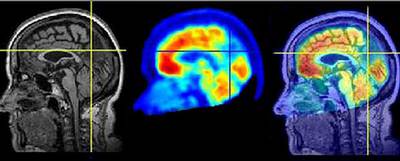

Las metas más inmediatas son descifrar los mecanismos que rigen comportamientos sincronizados en algunas áreas cerebrales con la esperanza de desvelar las incógnitas sobre dos grandes anomalías asociadas a una sincronización aberrante. La primera es aquella en la que se produce un exceso de coordinación cerebral: "Enfermedades como la epilepsia y el Párkinson se caracterizan porque hay un exceso de sincronización neuronal", explica García Ojalvo. "En un ataque de epilepsia las neuronas se comportan de una forma similar a una orquesta en la que todos los intérpretes tocaran igual: sin distinciones, ni tonalidades". El grupo parisiense es el que está especializado en epilepsia y, mediante electroencefalogramas intracraneales y resonancias magnéticas del cerebro, trabaja en la detección del epicentro de la sincronización anormal, donde suele estar el foco del problema.

En la enfermedad de Alzheimer se produce el efecto opuesto. "Las neuronas corticales mueren, disminuyendo la conectividad anatómica cerebral y su capacidad para sincronizarse", resume García Ojalvo. "Estudiamos a personas entre 65 y 85 años, algunas con pérdidas de memoria normales propias del envejecimiento y otras que padecen deterioros cognitivos leves que suelen preceder a la enfermedad de Alzheimer", añade Cantero. "Estudiamos la integridad funcional de su cerebro mediante tomografía por emisión de positrones y registros electroencefalográficos con 64 sensores en la corteza cerebral".

Pero los análisis no acaban ahí: "Al mismo paciente se le realiza una resonancia magnética de cerebro, a partir de la cual calculamos el volumen de algunas estructuras del sistema nervioso claves para la cognición", dice Cantero. En la actualidad se puede cuantificar cómo la corteza cerebral, la parte más superficial del sistema nervioso, va perdiendo espesor y, por tanto, funcionalidad en algunos pacientes de Alzheimer. "Es un signo de que algo podría estar funcionando mal", advierte.